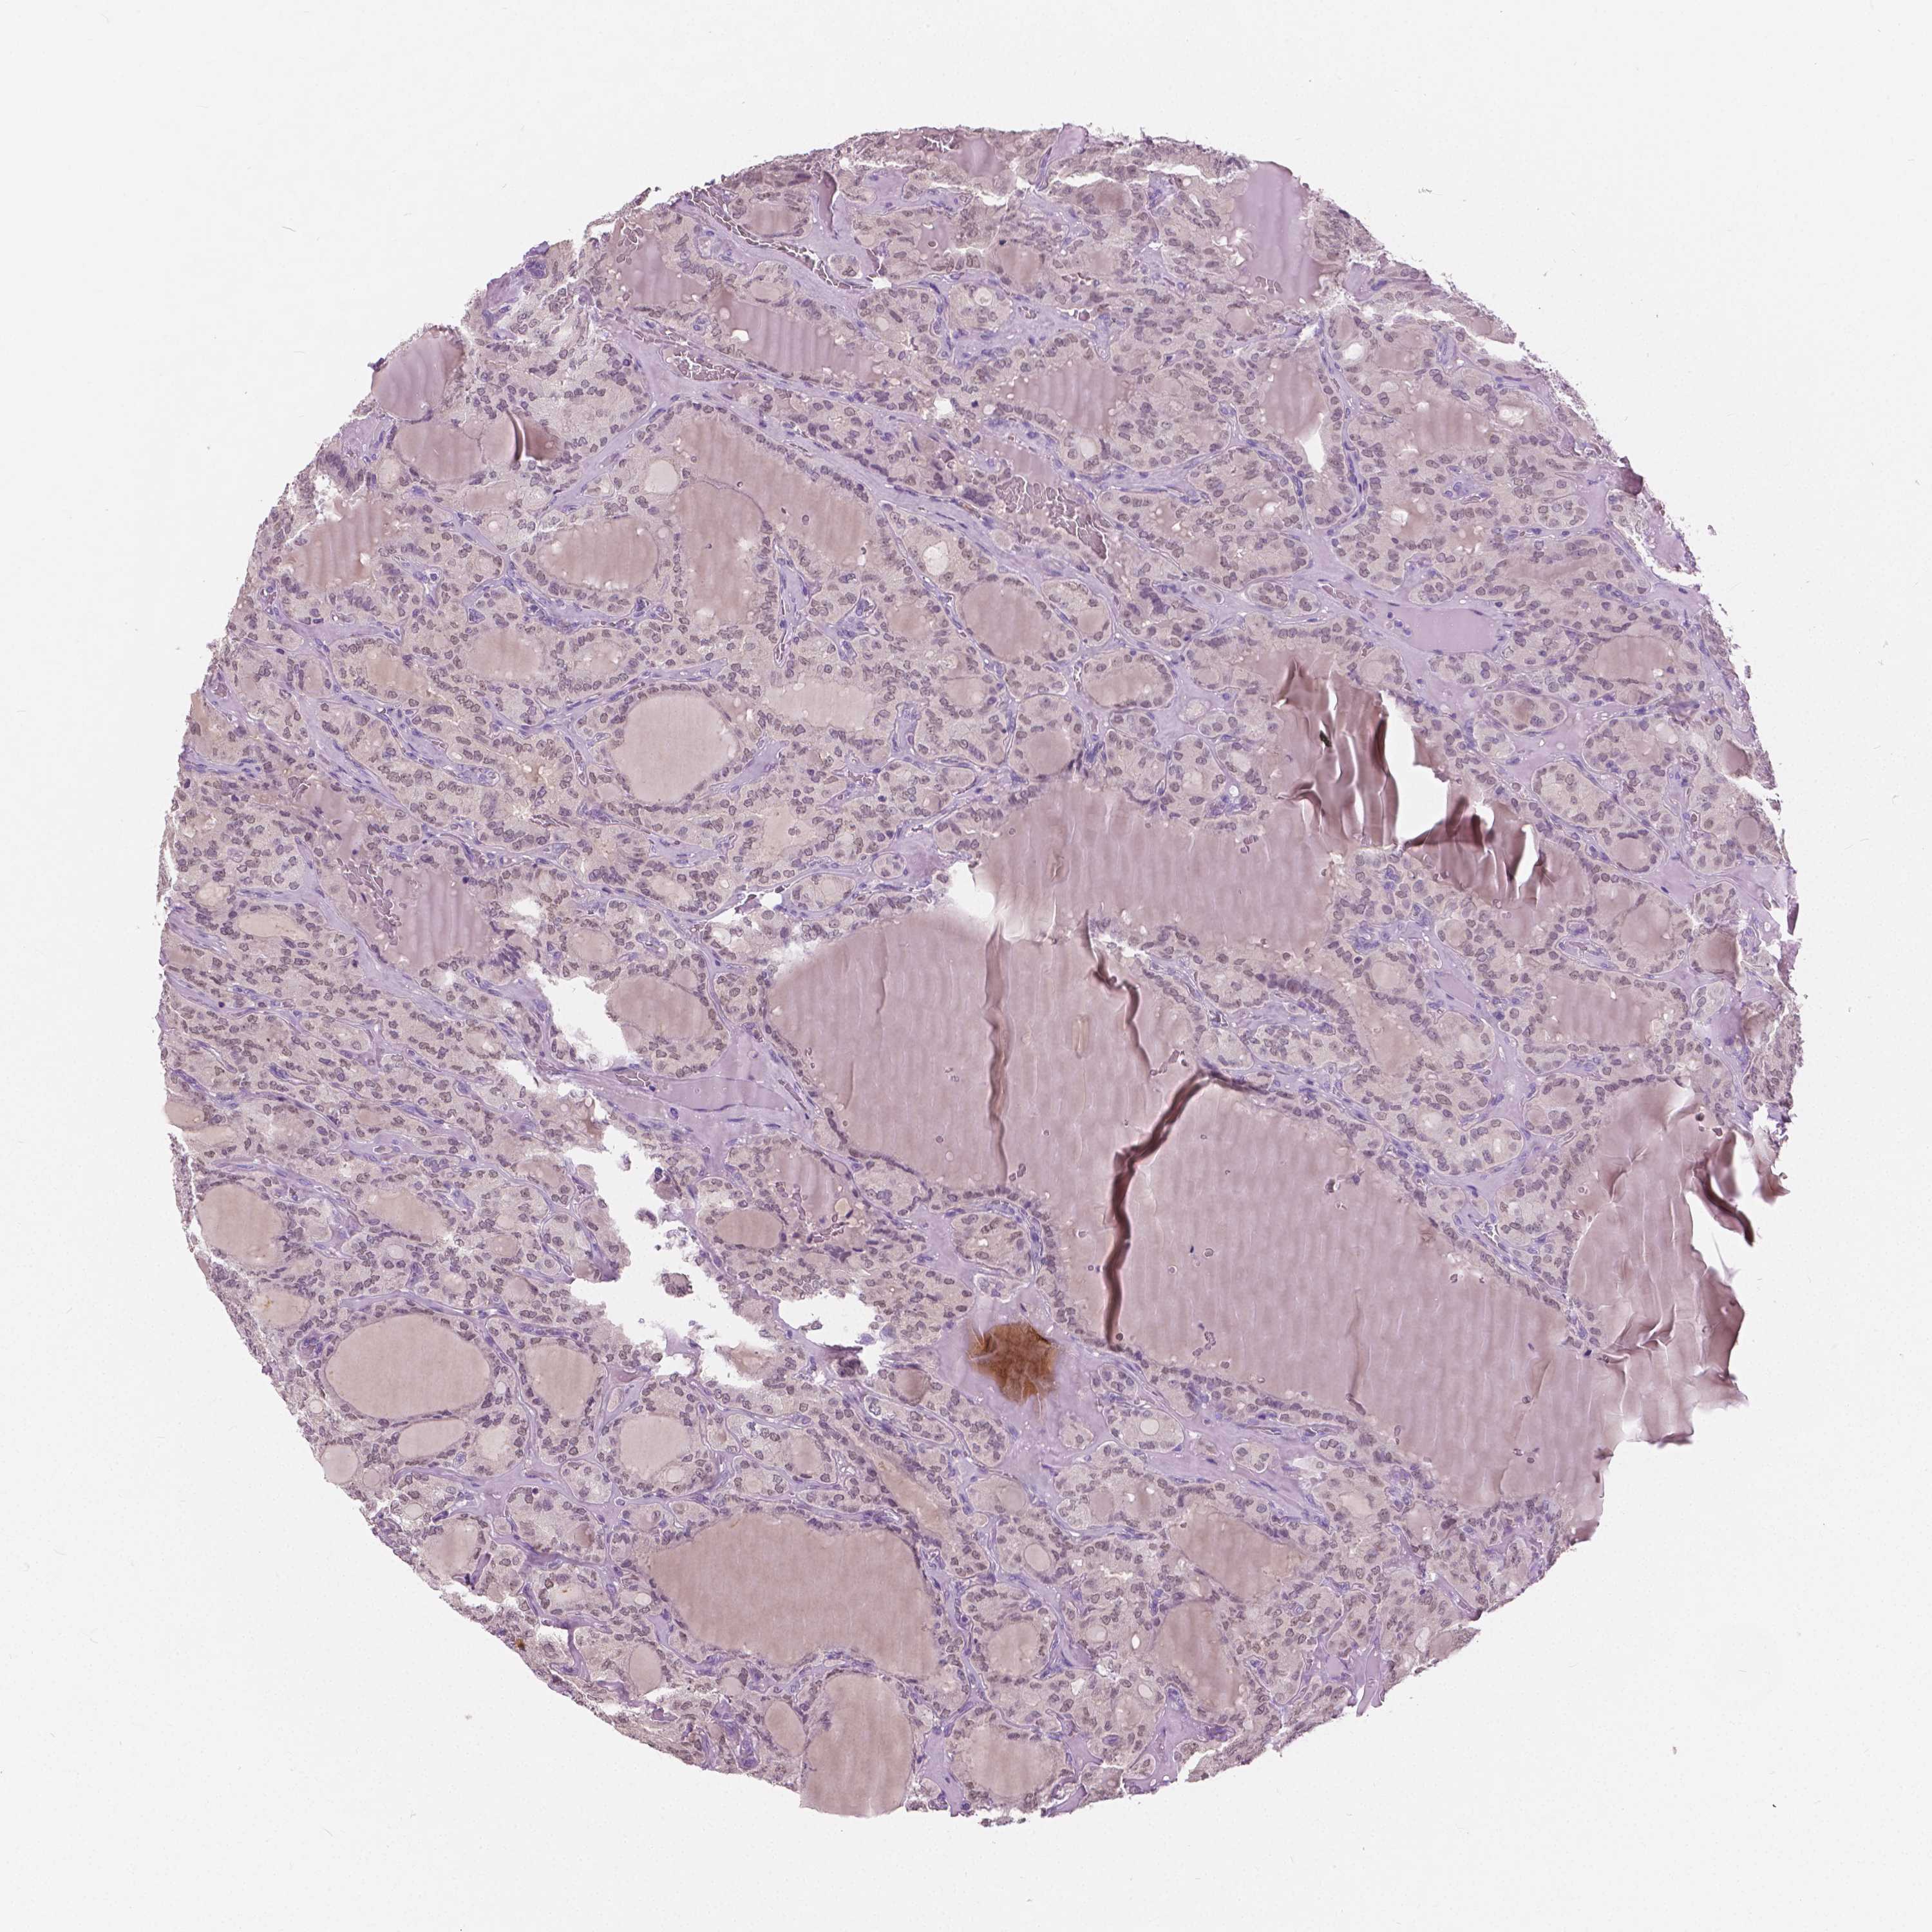

THYROID CANCER - Protein expressioni

A mouse-over function shows sample information and annotation data. Click on an image to view it in a full screen mode. Samples can be filtered based on level of antibody staining by selecting one or several of the following categories: high, medium, low and not detected. The assay and annotation is described here.

Note that samples used for immunohistochemistry by the Human Protein Atlas do not correspond to samples in the TCGA dataset.

Antibody stainingi

Antibody staining in the annotated cell types in the current human tissue is reported as not detected, low, medium, or high, based on conventional immunohistochemistry profiling in selected tissues. This score is based on the combination of the staining intensity and fraction of stained cells.

Each image is clickable and will lead to virtual microscopy that enables deeper exploration of all samples and also displays staining intensity scores, fraction scores and subcellular localization as well as patient and tissue information for each sample.

Antibody HPA035472

Antibody HPA035473

Antibody HPA064835

Staining

High

Medium

Low

Not detected

Intensity

Strong

Moderate

Weak

Negative

Quantity

>75%

75%-25%

<25%

None

Location

Nuclear

Cytoplasmic/membranous

Cytoplasmic/membranous,nuclear

Papillary adenocarcinoma, NOS

Follicular adenoma carcinoma, NOS